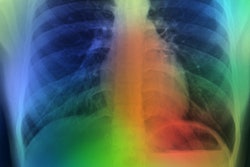

New research from South Korea shows that in countries using x-ray as part of population health check-ups, artificial intelligence (AI)-based software may improve the detection of lung nodules, according to research presented at the recent RSNA meeting in Chicago.

"We aimed to investigate if a commercial AI-based software may increase the detection rate of clinically significant, actionable lung nodules on chest x-rays in a health check-up population through a randomized, controlled trial. In addition, for this prospective trial we integrated AI-CAD into a commercial PACS (AI-PACS) and incorporated it into the real clinical work process," Nam told attendees at the meeting. "AI-based software enhanced detection of clinically significant lung nodules on chest x-rays without increasing false referral rate."